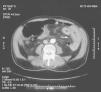

A 73-year-old man with hypertension and atrial fibrillation under warfarin was admitted with abdominal pain, distension, and dark blood hematemesis. He presented with anemia (Hb-8.4g/dL), prolonged prothrombin time and partial thromboplastin time with an INR >15. An endoscopy was performed. No lesions were identified, reporting only blood in the duodenum. A 150cm long pediatric colonoscope was introduced disclosing purple mucosa with ulcerations in the distal duodenum with spontaneous bleeding (Fig. 1a). As the endoscope passed into the jejunum, large and deeper ulcers were observed (Fig. 1b). Approximately 15cm distal to the Treitz angle (Fig. 1c), the bowel was extremely edematous presenting as circumferential ischemic necrosis. The ulcerations became deeper and about 25cm distal to the Treitz angle (Fig. 1d), there was complete luminal obstruction. The CT-scan showed a thickened wall of the distal duodenum and proximal jejunum, with edema and intramural hemorrhage (Fig. 2), without arterial or venous obstruction. Spontaneous small bowel hematoma is a rare complication of anticoagulant therapy. To the best of our knowledge, this is the first case of an intramural hematoma causing anticoagulant ileus, whose primary diagnosis was made through endoscopy.